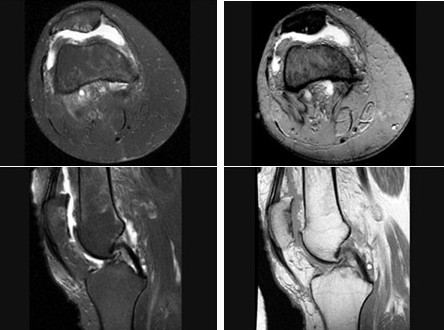

髌骨软骨软化症(如图)的治疗原则哪项是错误的